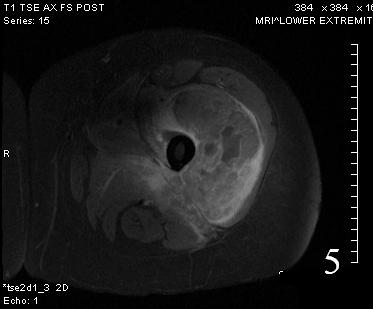

Fig. 5

Fig. 6

Fig. 5-6 Axial (Fig. 5) and coronal (Fig. 6)T1 post contrast MRI shows a heterogenous mass with enhancement post contrast